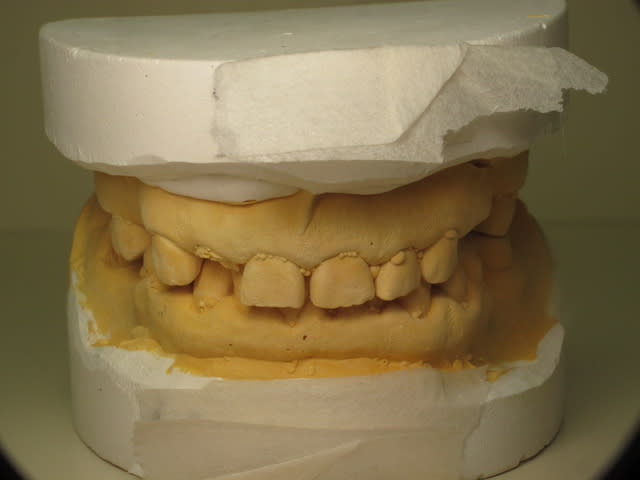

Le gros problème s'est l'occlusion. Côté gauche ça va et côté droit c'est la catastrophe. (voir les photos des modèles en occlusion)

Img 3756 soyc4i - Eugenol

Img 3757 voxbqp - Eugenol

Img 3758 xrmecb - Eugenol